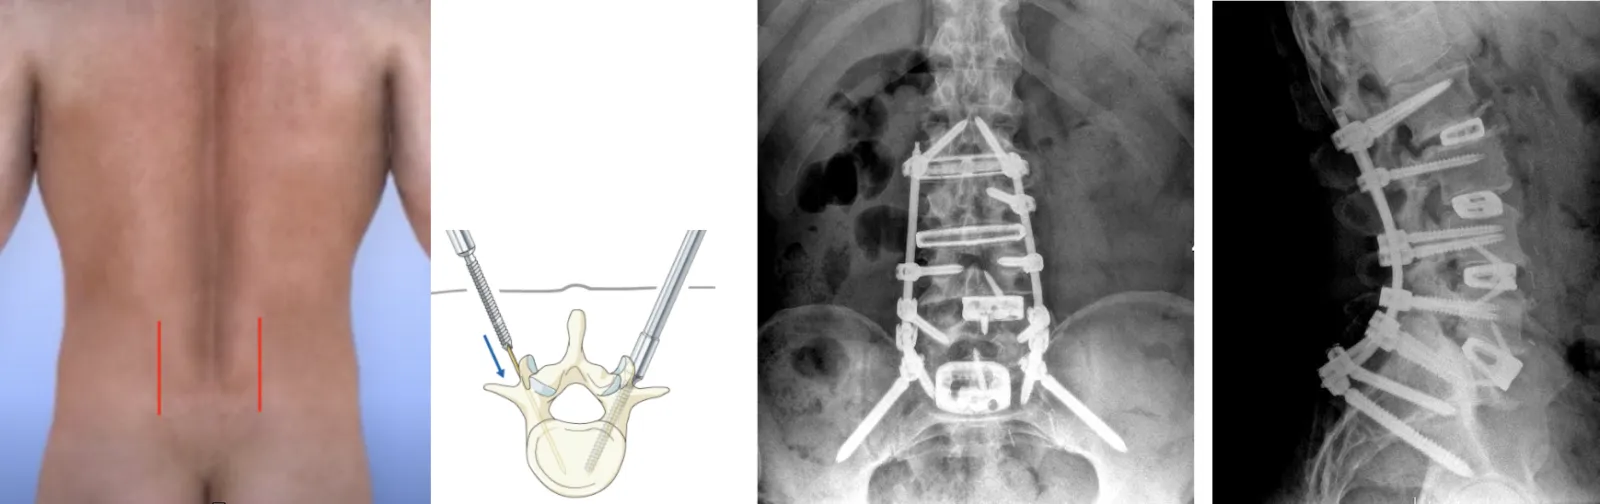

Posterior (Back) Procedure: Pedicle Screw Insertion:

- The ALIF and XLIF cages will be given extra support by placing screws and rods into the bones of the spine from the back (posterior).

- Sometimes this part of the surgery is done on a separate day than the ALIF and XLIF.

- For this part of the procedure, you will be repositioned on the table lying face down.

- Multiple small incisions will be made and X-ray or CT imaging is used to guide the screws through the small incisions into the bones that are above and below each of the fusion cages that were placed.

- If the fusion needs to extend into the thoracic spine, sometimes a six-inch incision is made to put bone graft onto the bones in that area and to place additional screws.

- The screws are then connected by rods to hold the spinal bones in their correct alignment as they heal and fuse through the ALIF and XLIF cages.

- The screws and rods will be placed from the top bone being fused down to the bottom bone being fused, typically S1. Sometimes screws are also placed into the pelvis through S2 to provide additional stability and fixation to prevent screw loosening.